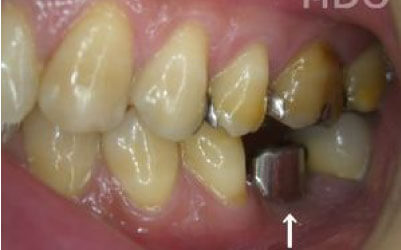

2 歯が傾いてくる、落ちてくる

歯は互いに支え合い、バランスを保っています。そのため、歯が抜けると支えがなくなり、抜けた部分の両隣の歯が傾いたり、上の歯が下に移動してきたりすることがあります。